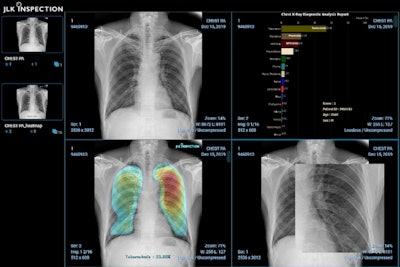

JLK's AI-based lung disease analysis algorithm JLD-02K allows doctors to make tuberculosis diagnoses more effectively. The software aims to address the problem of low radiologist capacity while also reducing screening expenses.

JLD-OK is an AI-enabled lung disease analysis software. Image courtesy of JLK Inspection.

JLD-02K doesn't have to run on a high-end workstation and can instead be used on mini personal computers or laptops, according to the company.